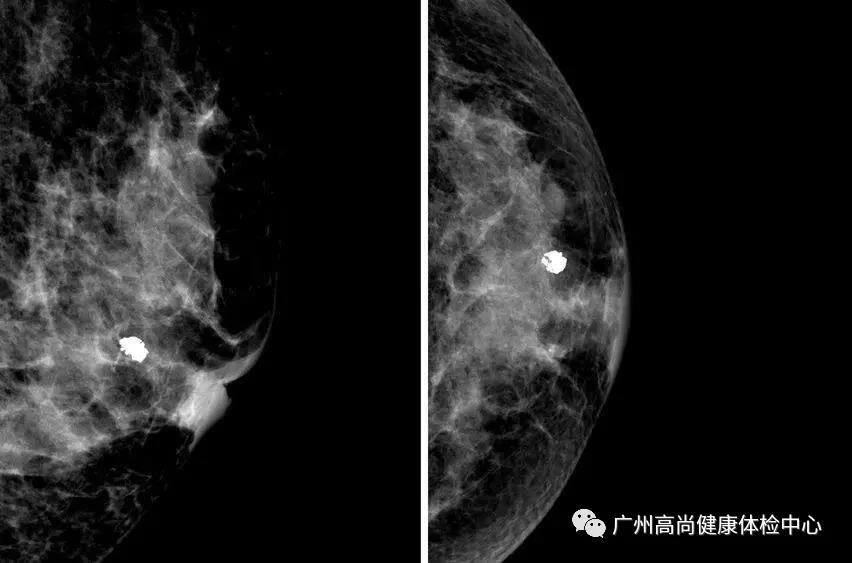

乳房的鈣化點(diǎn)大部分都是良性的,或伴有其他良性病變,如乳腺增生。所以,乳房鉬靶上如果看到大大的白點(diǎn),通常就是良性鈣化點(diǎn),如纖維腺瘤就常常會在鉬靶的影像上出現(xiàn)爆米花狀的粗糙大白點(diǎn)。

因此,惡性鈣化點(diǎn)的特點(diǎn)是:聚集很緊密,簇聚于局部區(qū)塊,且鈣化點(diǎn)很小,形狀不規(guī)則,每個點(diǎn)都不太一樣,或有針尖狀、小桿狀、分叉狀、簇狀及泥沙樣多屬于惡性病變。